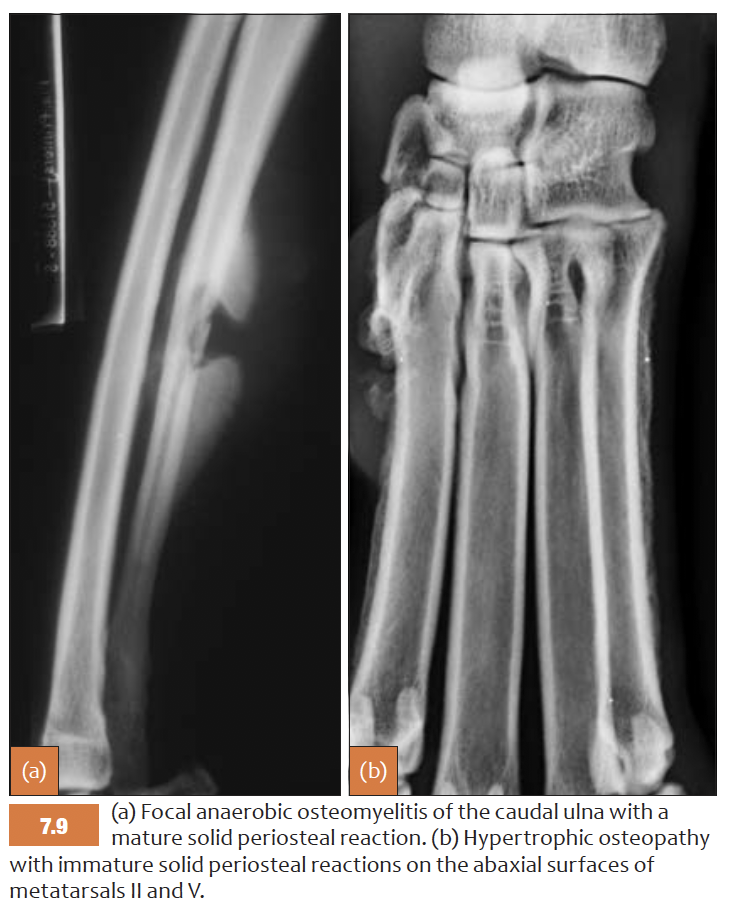

List features of SOLID periosteal reaction

=> the latter can be associated with neoplasoia

List features of lamellar (parallel) periosteal reaction

E.g osteomyelitis, neoplasia, hypertrophic osteopathy